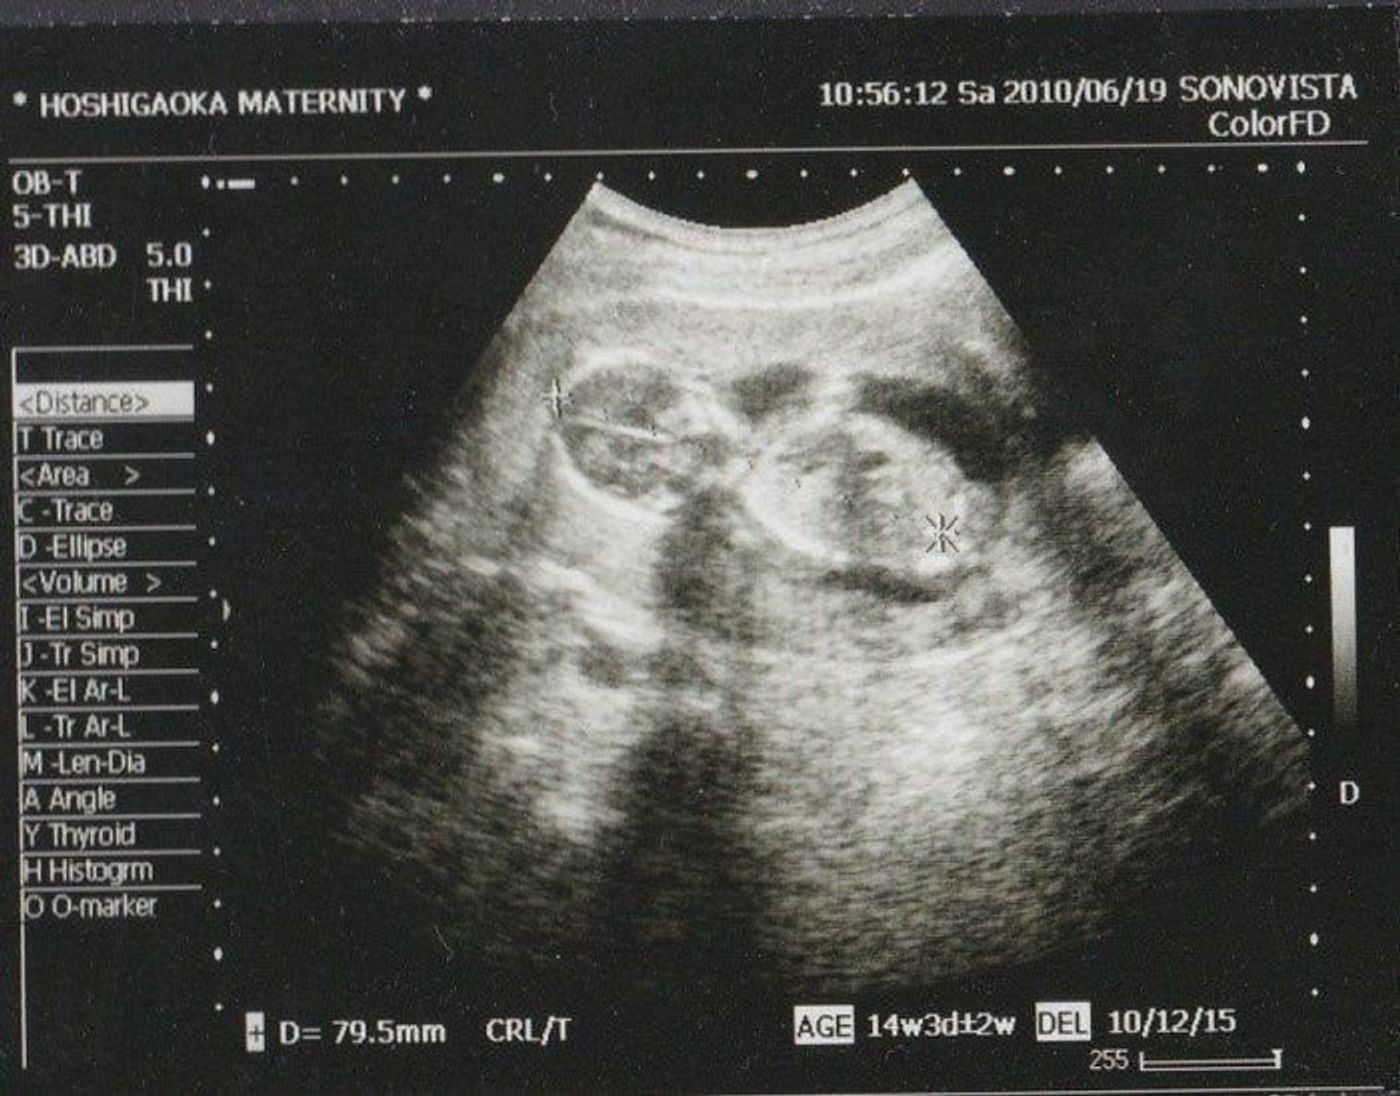

14週 エコー 男の子

妊娠16週5日(16w5d)で性別がわかった! 妊娠16週5日(16w5d)のエコー画像 妊娠16週で性別が男の子と確定したエコー画像 PR出産準備が10%オフ!Amazonベビーレジストリに登録しよう! 流産リスクなしの出生前検診って知ってる?妊娠14週3日(14w3d)の赤ちゃんのエコー写真です。投稿も募集しています。 性別も聞いてみるとシンボルがはっきり見えて 男の子だと言われました! こんなに早くわかるとは思ってなかったので びっくりしました!